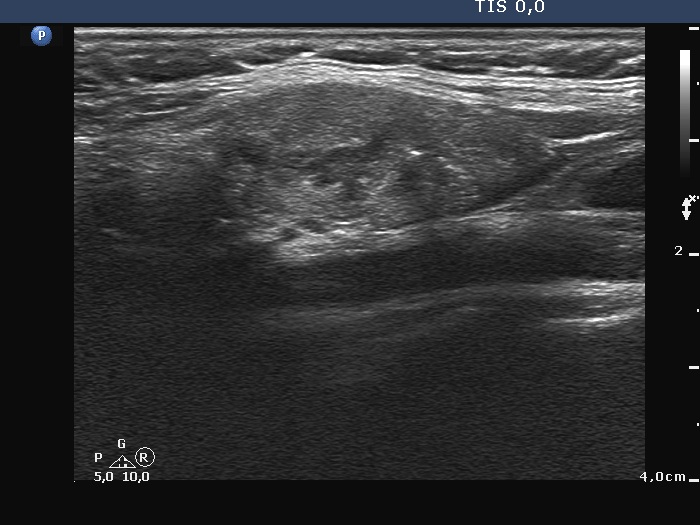

Ultrasonography. There was no thyroid tissue in the thyroid beds. Approximately 7 cm above the thyroid in the left side of the neck there were multiple, moderately hypoechoic lesions which presented tiny cystic areas. They had vascularity but did not have capsule.